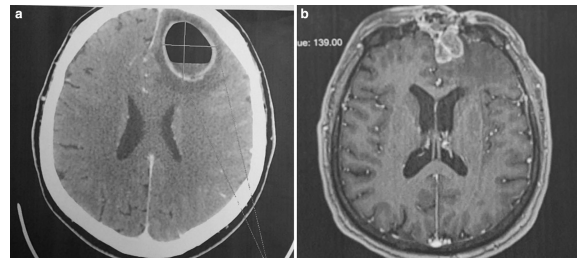

در دوره ی دوم (۱۹۷۹-۱۹۹۹)، هر دو سینوزیت پارانازال و عوارض داخل جمجمه با استفاده از توموگرافی کامپیوتری (CT) تشخیص داده شدند. این روش امکان تعیین محل دقیق تغییرات التهابی در سینوس ها را فراهم کرد. سی تی قادر به ارزیابی دقیق محل و شکل آبسه های مغزی و یا آبسه های چندگانه، آبسه ی اپیدورال، آمپیم ساب دورال و ناحیه اطراف ادم مغزی با جابجایی بطنی همزمان بود و همچنین اثربخشی درمان را پایش کرد.

در ۲۵ بیمار، آبسه در سمت راست بود که شایع ترین عارضه ی یافت شده در تمام دورهها بود (۹ نفر در دوره ی اول، پنج مورد در دوره ی دوم و ۱۱ نفر در دوره ی سوم). تنها در یکی از بیماران مبتلا به آبسه ی لوب فرانتال چپ، آبسه های اپیدورال جمجمه و آمپیم ساب دورال وجود داشت. در بیمار دیگری، آبسه های فرانتال دو طرفه بودند. شانزده بیمار با آبسه ی اپیدورال (هفت، دو و هفت نفر به ترتیب در هر کدام از دوره های اول، دوم و آخر)، و نه بیمار با آمپیم ساب دورال (سه، یک و پنج نفر به ترتیب در هر کدام از دوره های اول، دوم و آخر) تشخیص داده شدند (شکل ۳).

در یکی از بیماران، چندین آبسه مغزی در لوب فرونتال و جداری مشاهده شد (شکل ۴). سه بیمار با ترومبوز سینوس علامت دار (۰، ۲ و ۱ در دوره های مربوطه) در کلینیک بستری شدند. دو بیمار سربریت داشتند. پانزده بیمار مبتلا به مننژیت بودند: هشت نفر با سبب شناسی استافیلوکوک یا استرپتوکوک و یک نفر هم با سبب شناسی ویروسی تشخیص داده شده. در دو بیمار، مایع مغزی نخاعی استریل بود (جدول ۲ و ۳).